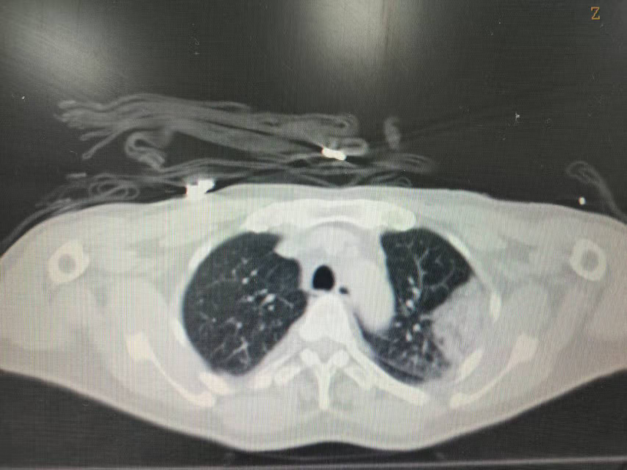

患者为中年男性,曾接受肾盂癌根治手术,术后因肿瘤复发开始免疫治疗。治疗期间,患者肺部出现孤立性转移病灶缓慢增大(寡进展)。经多学科讨论,肿瘤内科决定采用冷热多模态消融技术对肺部转移病灶进行处理。术中根据规划路径,在CT引导下将消融针经皮穿刺至病灶位置;行2个冻融循环,复查消融范围超出病灶边界5mm;复温状态下逐步拔出穿刺针。整个手术耗时约1小时,术中患者无疼痛刺激及咯血,术后无气胸。术后第二天顺利出院。

术后即刻CT平扫,冷冻范围超过病灶边界5mm